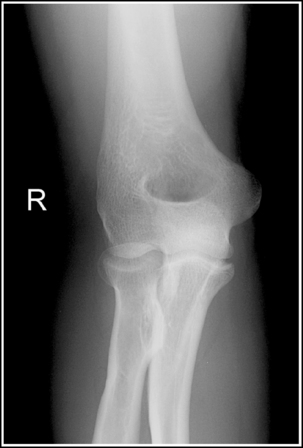

The elbow is positioned in an AP projection. The medial and lateral humeral epicondyles are demonstrated in profile at the extreme medial and lateral edges of the distal humerus, and the radial head is superimposed over the lateral aspect of the proximal ulna by approximately 0.25 inch (0.6 cm). The coronoid process is demonstrated on end.

• An AP projection of the elbow is obtained by supinating the patient's hand and externally rotating the forearm and humerus until an imaginary line drawn between the humeral epicondyles is parallel with the IR (Figure 4-67). This positioning places the proximal radius anterior to the ulna.

• Detecting elbow rotation. Rotation of the elbow is a result of poor humeral epicondyle positioning and can be identified on an image when (1) the epicondyles are not visualized in profile, (2) the radial head is demonstrated with more or less than 0.25 inch (0.6 cm) superimposition of the ulna, and (3) the coronoid process is seen in profile. The smaller, lateral humeral epicondyle is more sensitive to rotation, moving out of profile with only a slight degree of elbow rotation. If the epicondyles are not demonstrated in profile, evaluate the degree of radial head superimposition of the ulna to determine how to reposition for an AP projection. If more than 0.25 inch (0.6 cm) of radial head is superimposed over the ulna, the elbow has been internally rotated (see Image 74). If less than 0.25 inch (0.6 cm) of the radial head is superimposed over the ulna, the elbow has been externally rotated (see Images 75 and 76).